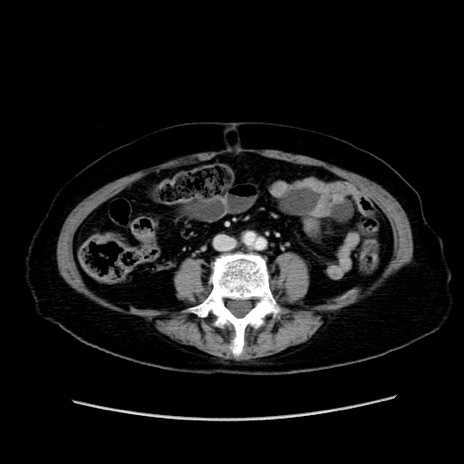

症例19(横断像)

症例

冠状断像

【症例】80歳代女性

【主訴】下腹部痛

【現病歴】約8時間前より下腹部痛の出現あり、救急外来受診。

【既往歴】両側付属器切除

【身体所見】意識清明、下腹部正中に手術痕あり、その部位に一致して圧痛と反跳痛あり。腸蠕動音は亢進。

【データ】WBC 9300、CRP 0.15